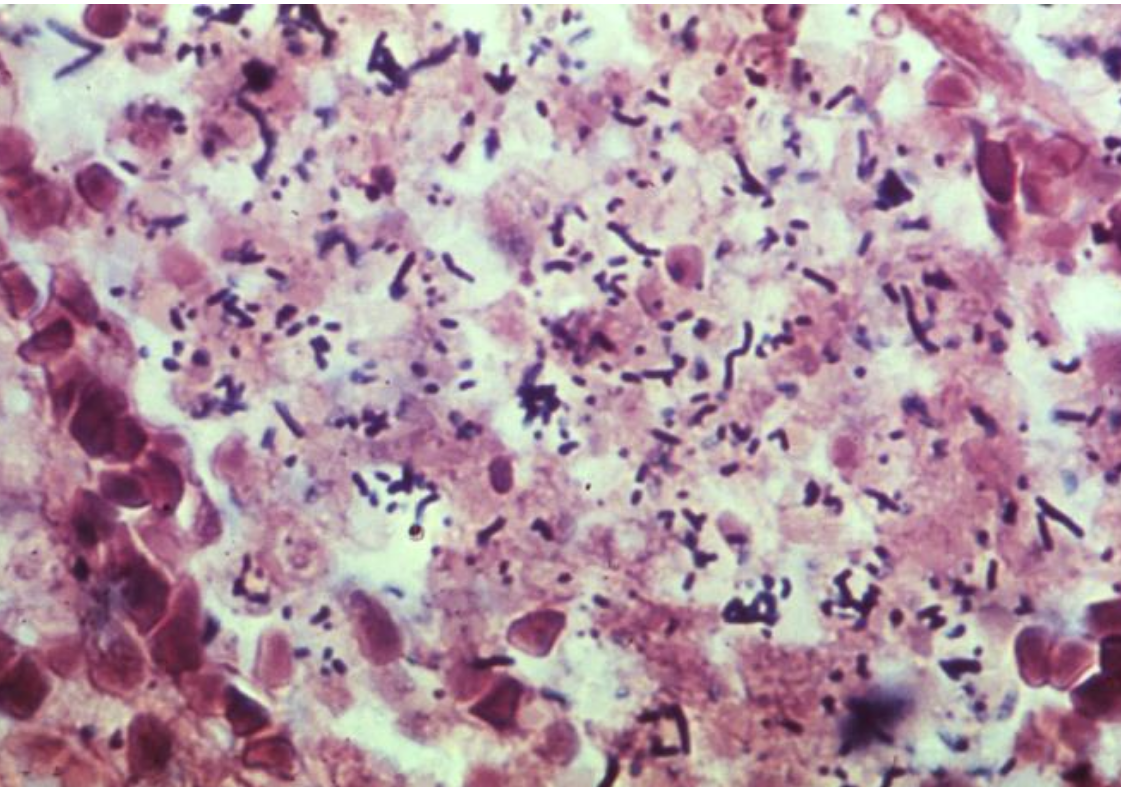

Листериоз фото

Листериоз фото 115 фотографий